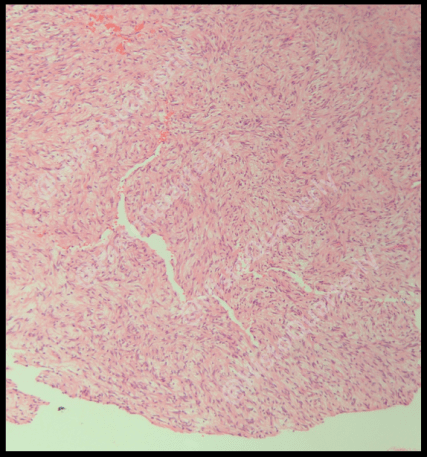

An additional feature that may be seen in a schwannoma is cystic spaces lined by Schwann cells, which can resemble glands or dilated lymphatics. Where this feature is quite pronounced, the schwannoma may be classified with the prefix of “pseudoglandular”. I don’t have an example of a case with florid cysts but I did stumble upon this case with a couple of them neighbouring each other in the same field:

A low power H&E showing cysts within a schwannoma

A medium power H&E taking a closer look at the cysts lined by Schwann cells.